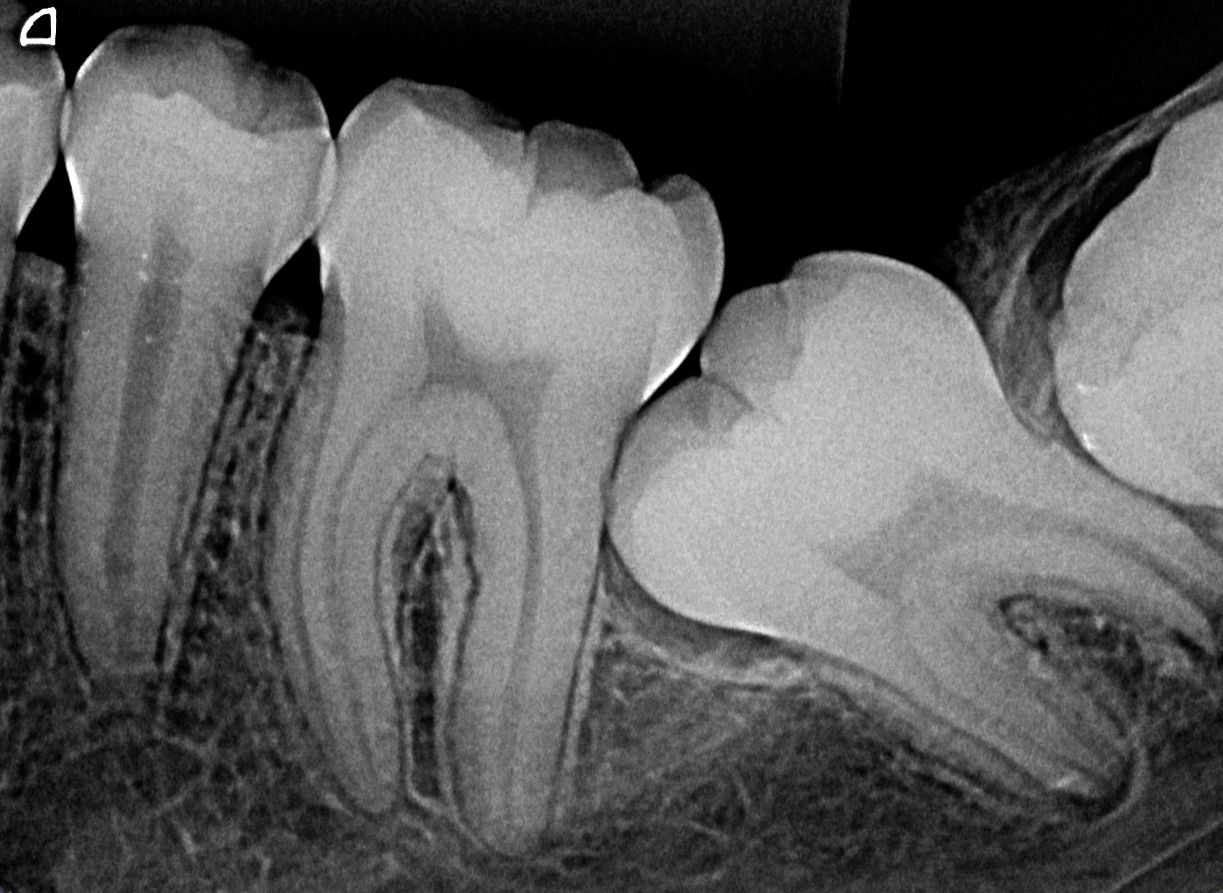

Rx Periapical Digital

Es una radiografía que se ubica dentro de la boca para tomar un diente específico, permite diagnósticos exactos relacionados con los dientes y sus tejidos de soporte.